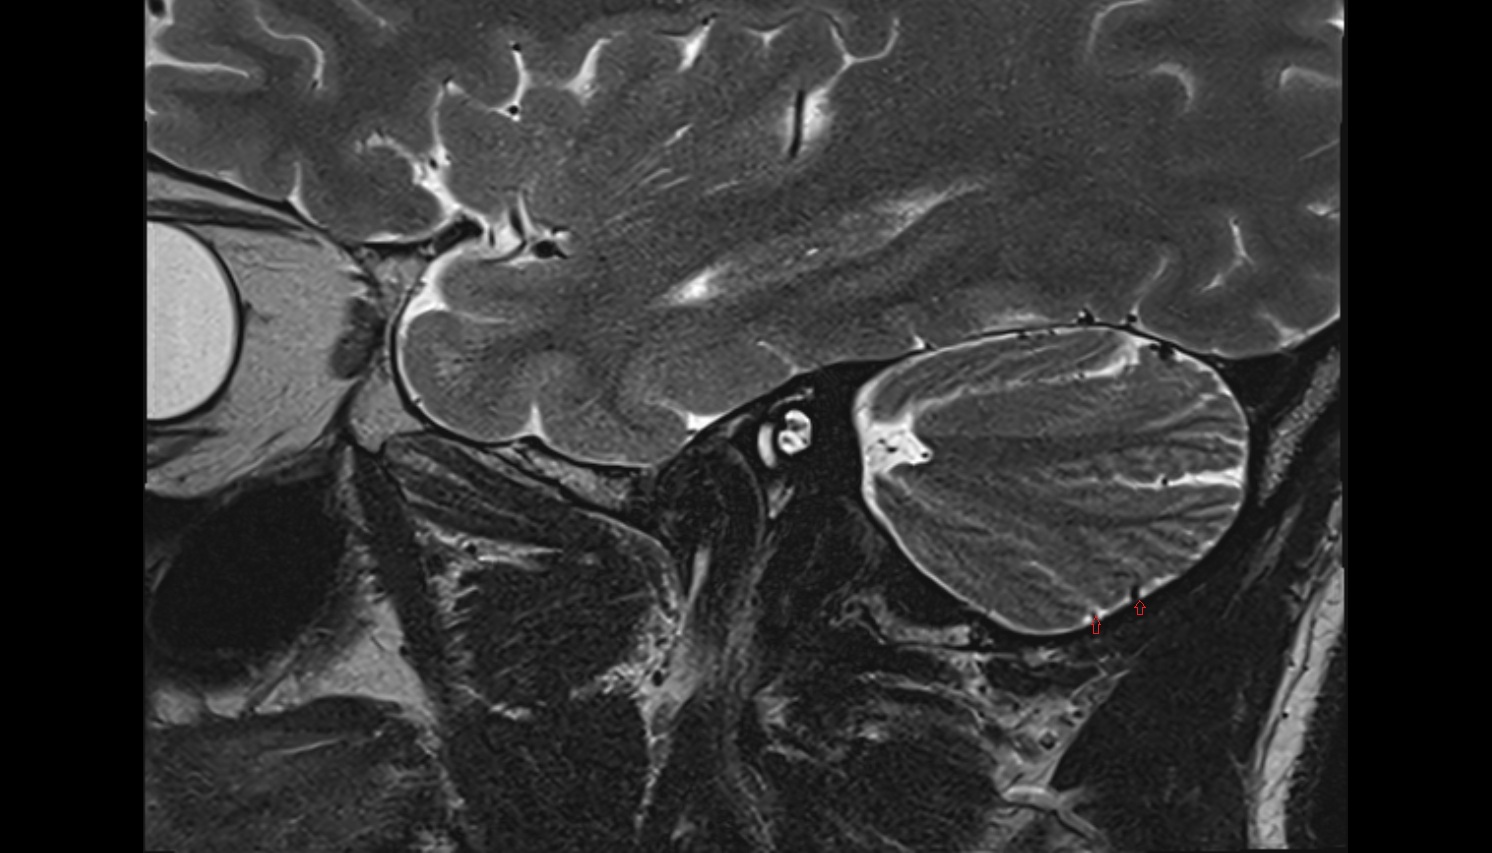

- Temporomandibular joint

- Mandibular condyle

- Mandibular fossa

- Articular disc of temporomandibular joint

- Articular eminence